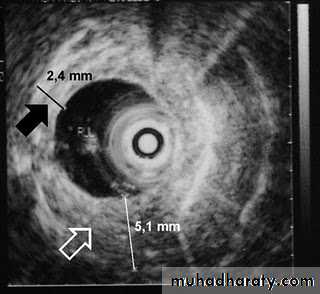

Computed Tomography

Contrast-enhanced CT plays an important role in the1.staging of esophageal carcinoma. to 2.determining the extent of the local tumor; 3.invasion of mediastinal structures; 4.involvement of supra clavicular, mediastinal, or upper abdominal lymph nodes

5. Assessment of the distant metastases

examination should extend from the thoracic inlet through the liver

Routine oral contrast material such as (gastrographine) or a negative intra luminalcontrast medium, such as water.

+/ - IV contrast injection

CT essential in the Dx & staging of the CA

CT finding of esophageal malignancy

1.Eccentric or circumferential wall thickening is greater than 5 mm.

2.Peri-esophageal soft tissue and fat stranding may be demonstrated.

3.A dilated fluid- and debris-filled esophageal lumen is proximal to an obstructing lesion.

4.Aortic invasion .

5.Osophageal CA is often metastatic at the time of presentation ( look for the LN & distal metastasis ) .